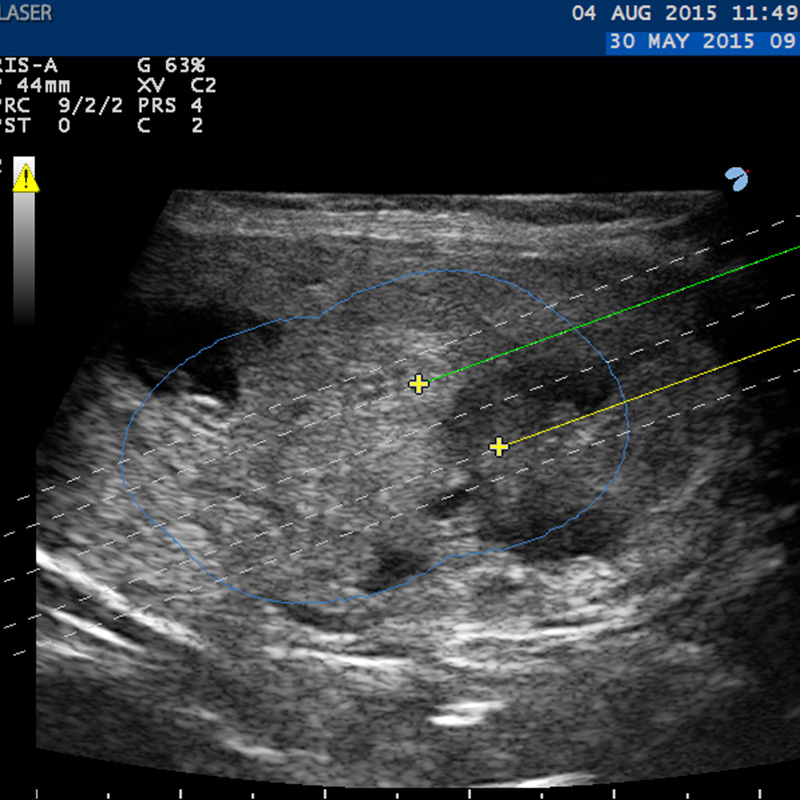

Modìlite consiste nell’inserimento di fibre ottiche (da 1 a 2 in funzione della dimensione del nodulo), per via percutanea, e nell’erogazione di energia laser per alcuni minuti che produce un riscaldamento del tessuto fino alla sua distruzione. Successivamente la progressiva riduzione del volume del nodulo tiroideo (riduzione del volume almeno >50% rispetto al volume basale ad 1 anno dal trattamento) indotta dai naturali meccanismi di rimozione dei tessuti necrotici del corpo umano determina la scomparsa dei sintomi compressivi e danni estetici del collo. La pianificazione del trattamento, l’inserimento degli aghi e il monitoraggio avvengono sotto guida ecografica.

Per facilitare la manovra di inserimento e pianificare il migliore posizionamento degli aghi nella lesione, ECHOLASER dispone di:

• dedicati Sistemi Guida multi-applicatore per sonde ecografiche dedicate al distretto anatomico della tiroide con i relativi Software Biopsia che visualizzano le linee guida sullo schermo;

• Software di Pianificazione del trattamento nell’unità ecografica che consente di scegliere, tra le differenti possibilità di trattamento, la più adatta e sicura ad ogni specifico caso e di controllare la corretta posizione degli aghi all’interno del nodulo.

1./2. Sonda Esaote LA332 con dedicato Sistema Guida multi-applicatore

3. Software Biopsia per inserimento applicatori / 4. Software di Pianificazione